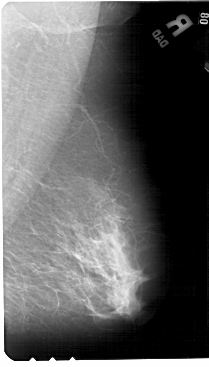

A_1444_1.RIGHT_MLO

RIGHT_CC LINES 5221 PIXELS_PER_LINE 2896 BITS_PER_PIXEL 12 RESOLUTION 43.5 NON_OVERLAY

RIGHT_MLO LINES 5491 PIXELS_PER_LINE 3121 BITS_PER_PIXEL 12 RESOLUTION 43.5 NON_OVERLAY